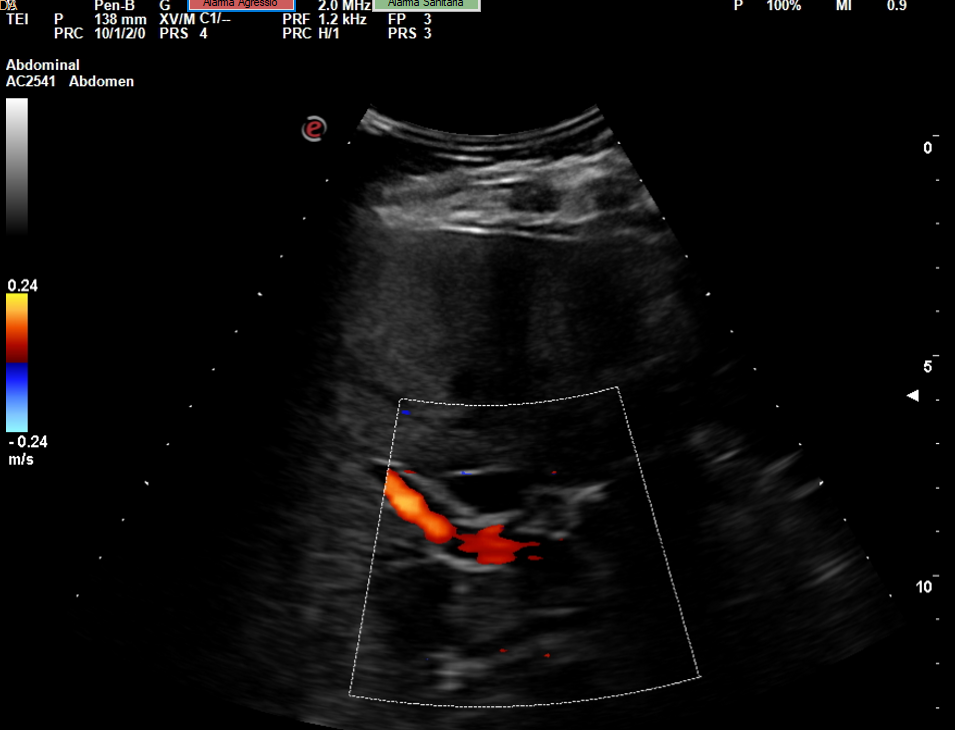

Descripción de los hallazgos ecográficos y las imágenes más relevantes para la resolución del caso

Se realiza la ecografía abdominal en el ambulatorio, donde se objetiva colelitiasis con el colédoco en el límite superior de la normalidad (4,4 mm), también presenta esteatosis hepática grado I. El resto de la ecografía no presenta hallazgos de interés.